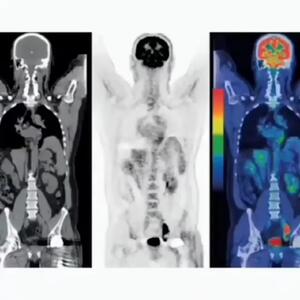

با افتتاح و بهرهبرداری از دستگاه پتاسکن (PET Scan) در هرمزگان، این استان به جمع معدود استانهای کشور پیوست که این خدمت تخصصی تصویربرداری پزشکی را با تعرفه دولتی به بیماران ارائه میدهند.

چند پروژه درمانی و خدماتی در فومن از جمله افتتاح دستگاه CT اسکن بیمارستان امام حسن مجتبی(ع)، آغاز عملیات اجرایی احداث بخش دیالیز، افتتاح پد بالگرد و غیره به بهره برداری رسید.

کردستان در ردیف ۶ استان برخوردار از دستگاه پتاسکن( تشخیص سرطان)

رئیس دپارتمان پزشکی هستهای پزشکی هستهای و تصویربرداری بیمارستان کوثر سنندج گفت: کردستان ششمین استاد کشور در دریافت دستگاه pet scan پیشرفته از نوع ۲۰۲۱ است که نشان از اهمیت و توجه به تجهیزات پزشکی پیشرفته در استان است.

آمادگی های لازم برای اسکن هسته ای قلب

اسکن هسته ای قلب یکی از روش های پیشرفته تصویربرداری برای شناسایی مشکلات قلبی است. این مطلب به نکات مهمی جهت آمادگی اسکن هسته ای قلب اشاره دارد.